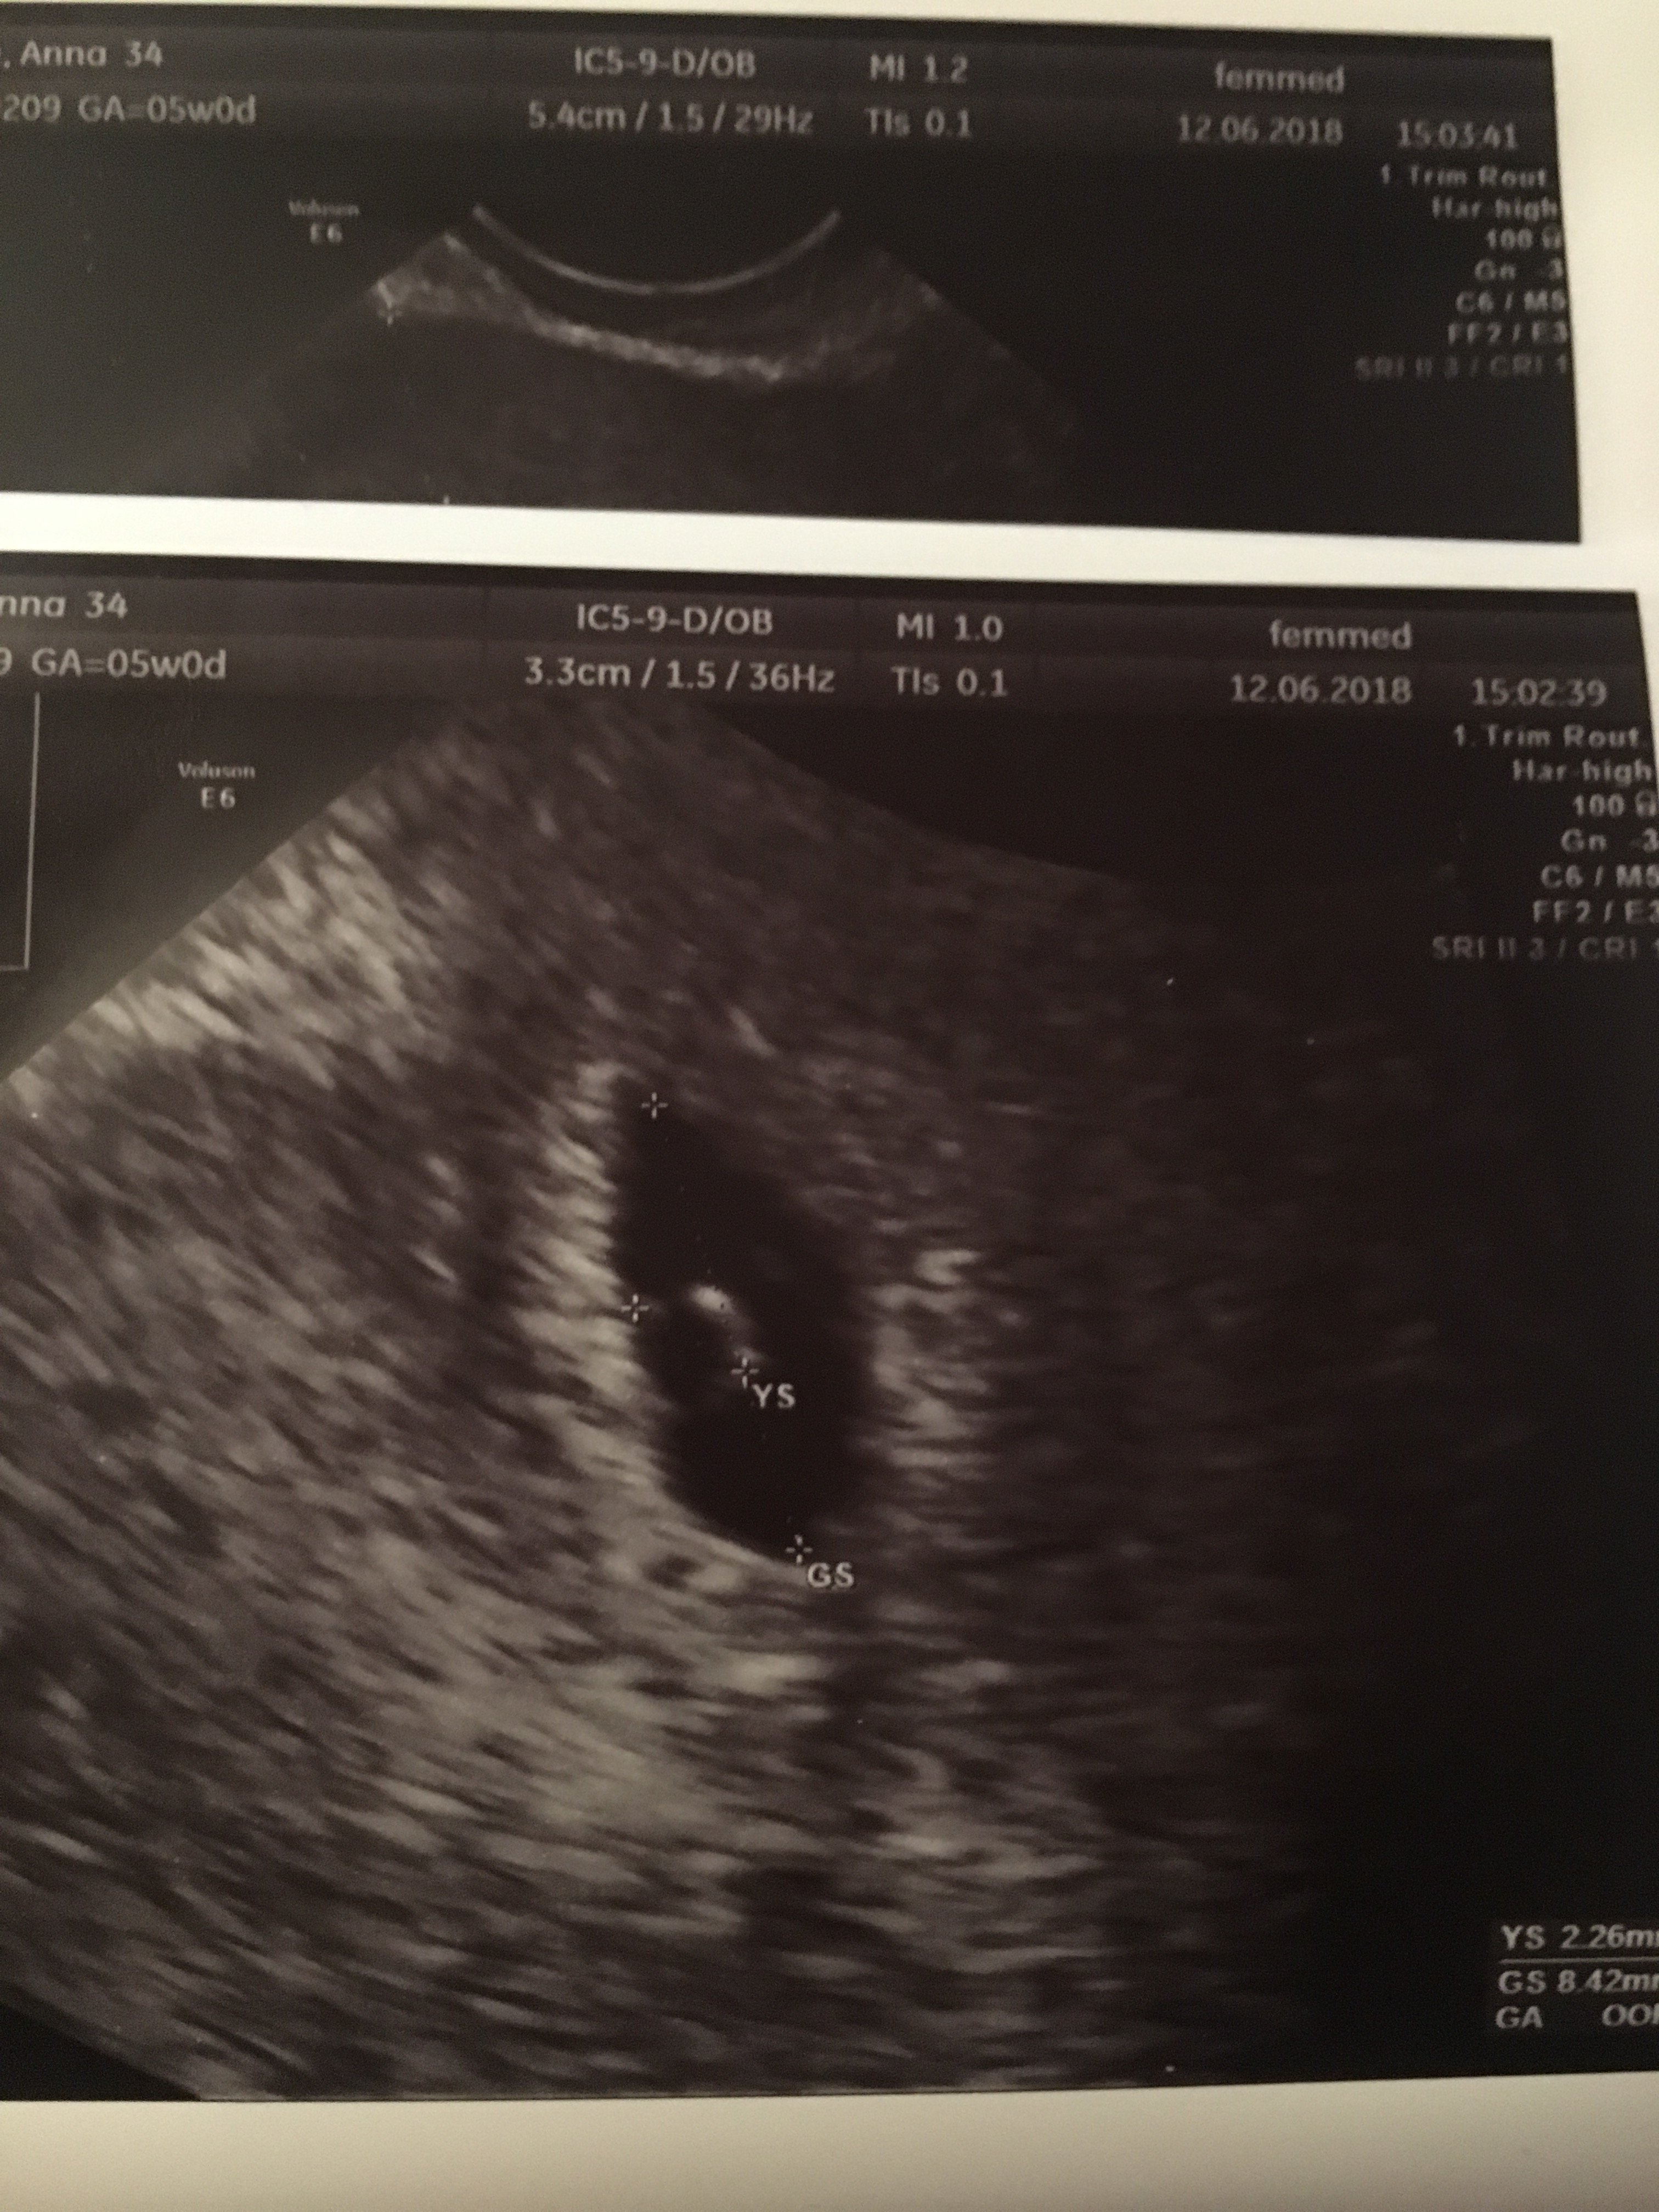

Czyli juz w 4+ kilka dni wg usg mialas pęcherzyk żółtkowy, dobrze rozumiem? Bo to szybciutko i na pewno wszystko będzie ok :)

Dokładnie tak [emoji4] mam nadzieję, że tak będzie...

To dzisiejsze usg